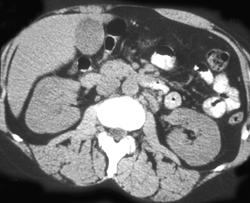

Oncocytoma